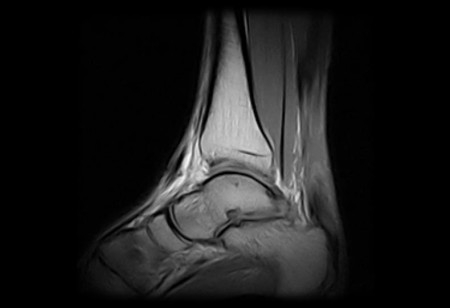

Az Achilles ín szakadása bevérzéssel